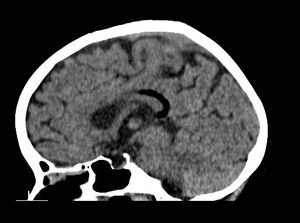

75-year-old male presented with left-sided weakness, headache, and altered sensorium.